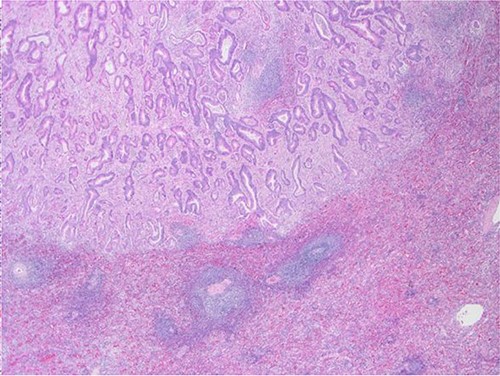

The definitive pathological report revealed adenocarcinoma metastases with morphology and immunophenotype compatible with an intestinal origin, both in splenic parenchyma and in uterine myometrium (see Figs 1–8).

Surgical specimen: splenectomy; microscopy, HE; spleen parenchyma infiltrated by well-formed neoplastic glandular structures composed of cells with ‘pencillated’ and atypical nuclei, with nucleoli, apoptosis and mitotic figures, consistent with an intestinal origin (metastatic colorectal adenocarcinoma).

Surgical specimen: splenectomy; microscopy, HE; spleen parenchyma infiltrated by well-formed neoplastic glandular structures composed of cells with ‘pencillated’ and atypical nuclei, with nucleoli, apoptosis, and mitotic figures, consistent with an intestinal origin (metastatic colorectal adenocarcinoma).